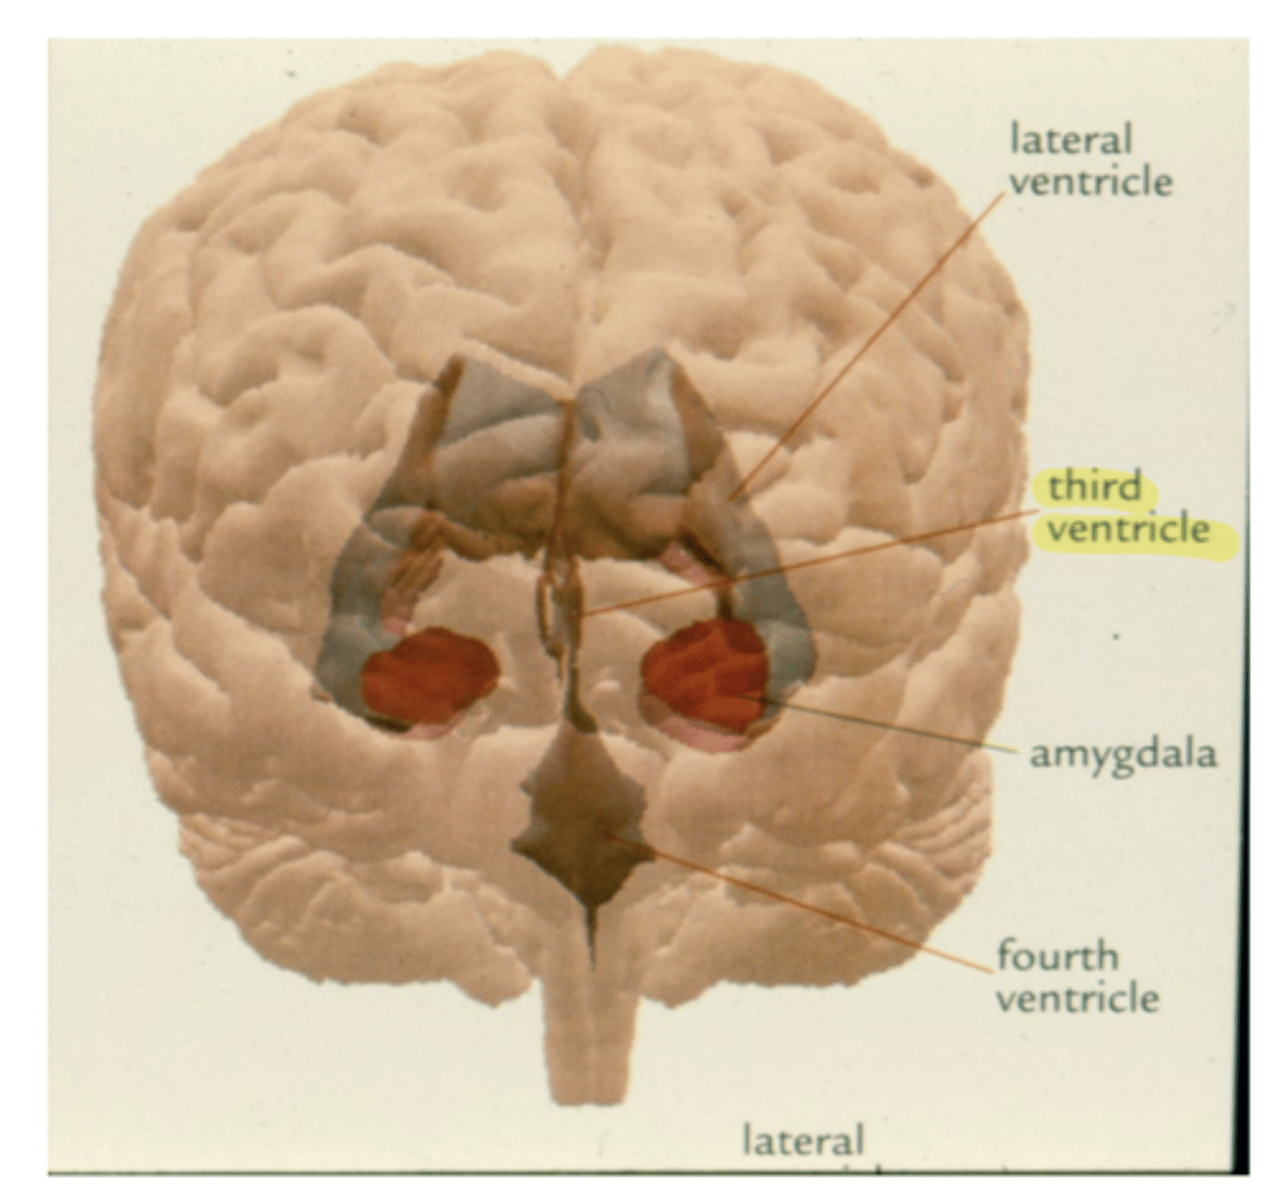

What are the lateral walls of the third ventricle?

thalamus and hypothalamus

What is the massa intermedia?

the neuronal connection between the two thalami

What does the massa intermedia pass through?

3rd ventricle

What are the three nuclear complexes of the thalamus?

1. anterior nuclei

2. medial nuclei (connected by massa intermedia)

3. lateral nuclei